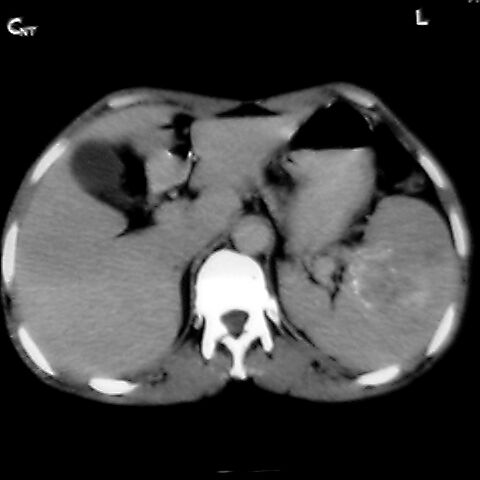

女 48岁 食道癌术前体检发现脾占位。

脾胀内部巨大低密度肿块,边界清或不清,中心坏死,轻度增强,内见散在钙化,结合食道癌病史多考虑:转移癌.

1肝右下叶小囊肿2右肾上极囊肿或错构瘤3脾脏不典型血管瘤可能性大.

脾脏低密度灶伴钙化,增强化明显,中心见液化坏死灶,强化延时明显。考虑血管瘤。转移瘤待排。

右肾见类圆形低密度影.结合病史.脾及右肾转移性ca可能性大